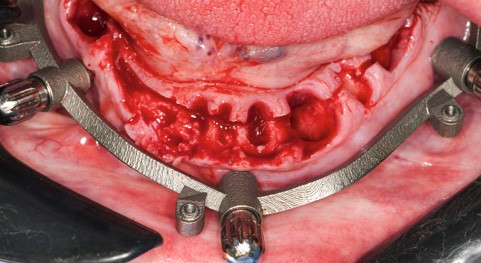

Un premier étage, appelé guide base, est fixé sur le maxillaire à implanter et servira de socle pour les étages supérieurs à empiler (fig. 2). Il doit être aussi rigide que stable pour supporter les contraintes pendant toute la durée de l’intervention : celles du forage implantaire comme celles des poses et déposes des étages supérieurs. Son bon positionnement est donc crucial car il déterminera celui des autres étages. Il peut également servir de repère en fin de procédure, tel un guide de scannage, pour réaliser une empreinte optique (fig. 3). Les appuis sont aussi divers qu’avec un guide statique conventionnel :